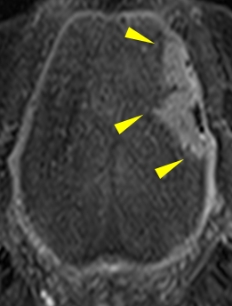

一般的に舌がんの術前の画像診断ではMRIが有用とされており、腫瘍のサイズや深さの評価が行われます。CTを使った従来の撮影方法では、歯科金属の影響でうまく腫瘍を描出することができませんでした。我々は超高精細CT(図1)を用い撮像の方法を工夫することで、舌がんをできるだけ正確に測定する試みを行っています。そうすることで非常に細かい、いわゆるキレイな画像を作成することができ、腫瘍の境界を鮮明に描出し、腫瘍のサイズをより正確に測定することが可能になりました(図2)